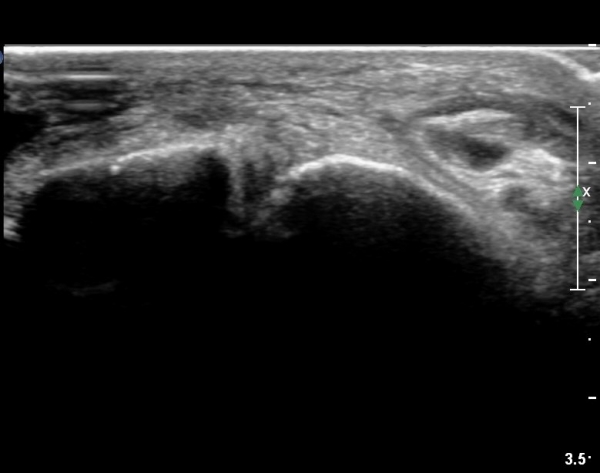

¸»´Ü °æ°ñºñ°ñÀδëÀÇ ÆÄ¿­ÀÌ °üÂûµÇ°í(»çÁø 4, 5)

ºÎÇÏ°Ë»ç ½Ã °æ°ñ°ú ºñ°ñÀÌ ¹ú¾îÁö°í ¼ö¾×ÀÇ À̵¿ÀÌ °üÂûµÈ´Ù(÷ºÎµ¿¿µ»ó 1)